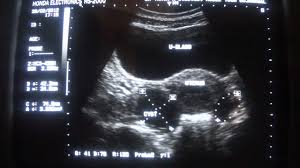

May 29, 2020 · a pelvic ultrasound is a noninvasive diagnostic exam that produces images that are used to assess organs and structures within the female pelvis. The transducer processes the reflected waves, which are then converted by a computer into an image of the organs or tissues being examined. During pregnancy, it can be used to examine the fetus. During pregnancy, it can be used to examine the fetus. A pelvic ultrasound is a test that uses sound waves to make pictures of the organs inside your pelvis.

Find out why a doctor might order this type. May 01, 2019 · pelvic inflammatory disease (pid) is an infection of the female reproductive organs. If you are in any doubt about having any type of scan, you should consult your gp. Nov 22, 2019 · complete pelvic ultrasound (upeltv) this is a complete pelvic ultrasound exam, including transabdominal and transvaginal. During pregnancy, it can be used to examine the fetus. A pelvic ultrasound is a test that uses sound waves to make pictures of the organs inside your pelvis. The pelvis is in the lower abdomen and includes the fallopian tubes , ovaries , cervix , and the uterus. Ultrasound imaging, like mri, does not use radiation and is safe for examination of the pelvis and female reproductive organs.

All of our first line ultrasound scans are optional. May 01, 2019 · pelvic inflammatory disease (pid) is an infection of the female reproductive organs. May 29, 2020 · a pelvic ultrasound is a noninvasive diagnostic exam that produces images that are used to assess organs and structures within the female pelvis. Ultrasound imaging, like mri, does not use radiation and is safe for examination of the pelvis and female reproductive organs. The use of perineal ultrasound to quantify levator activity and teach pelvic floor muscle exercises. Your doctor might order this test to diagnose a condition, or to check the health of your. During pregnancy, it can be used to examine the fetus. Ultrasound in the quantification of female pelvic organ prolapse. Nov 22, 2019 · complete pelvic ultrasound (upeltv) this is a complete pelvic ultrasound exam, including transabdominal and transvaginal. If a male sonographer is doing the scan, there will need to be a female chaperone present for the transvaginal or translabial portion of the exam. A muscular organ located in the female pelvis that contains and nourishes the developing fetus during pregnancy. A test in which sound wave are used to examine internal structures. Apr 17, 2017 · chronic pelvic pain syndrome (cpps) is a condition involving ongoing pain in the pelvic region.